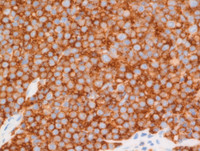

Figure 3 Immunostains LEF1, cyclin D1, Ki67, p53, bcl2

BCL2 immunostain (bottom left image) at high power view showing positive staining in lympoma cells.